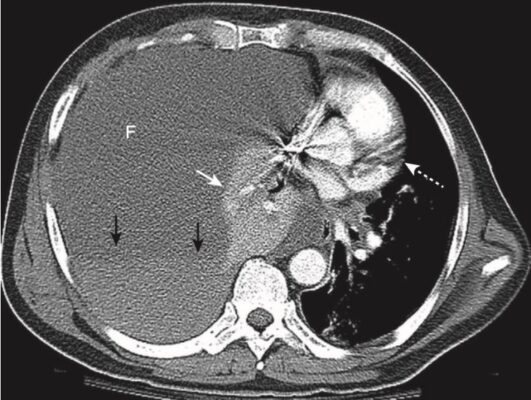

- Khi nửa ngực của một người trưởng thành chứa khoảng 2 L chất dịch, toàn bộ nửa ngực sẽ bị mờ (Hình 11).

- Khi chất dịch đầy khoang màng phổi, phổi có xu hướng bị xẹp thụ động (xẹp phổi).

- Trên phim chụp X quang phổi thông thường, các tràn dịch lớn tạo hình ảnh mờ đủ mức bao bọc và che khuất bệnh lý bên dưới ở phổi. CT là phương thức thường được sử dụng để đánh giá phổi bên dưới khi có tràn dịch lớn (Hình 12).

- Tràn dịch lượng lớn có thể hoạt động như một khối và làm dịch chuyển tim và khí quản ra xa bên bị mờ.